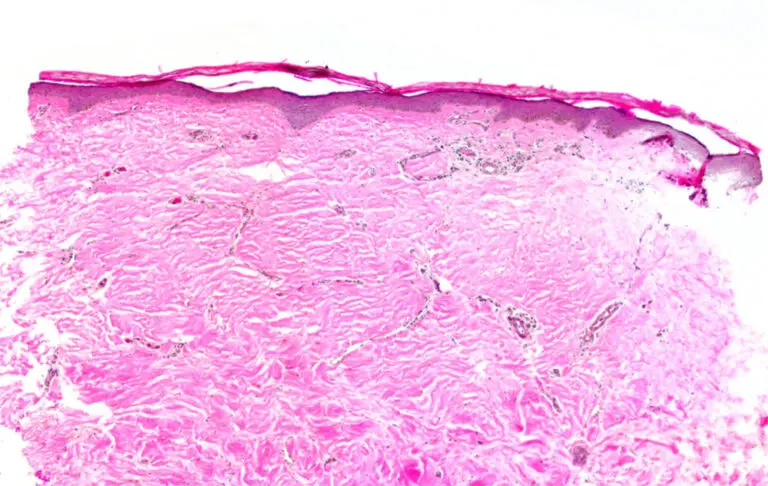

Because Kerecis is minimally processed and retains the fish’s natural skin structure – which is remarkably similar to human skin – it integrates quickly, enabling you to reduce time to definitive reconstruction or unlock options lower on the reconstructive ladder.

Our fish-skin grafts’ intact ECM components help enhance healing in damaged or hypovascularized tissue beds by rapidly incorporating and facilitating cellular ingrowth,[2,3] creating a healthy area ready for closure by secondary intention, autograft, or flap.

Poor graft integration and disorganized tissue remodeling can compromise patient outcomes. Kerecis’ 3D tissue structure provides a robust platform for fibroblast infiltration, promoting fast integration. This may help limit scarring, adhesion, and secondary contracture, [4,5,6] which can help restore and maintain function such as range of motion.